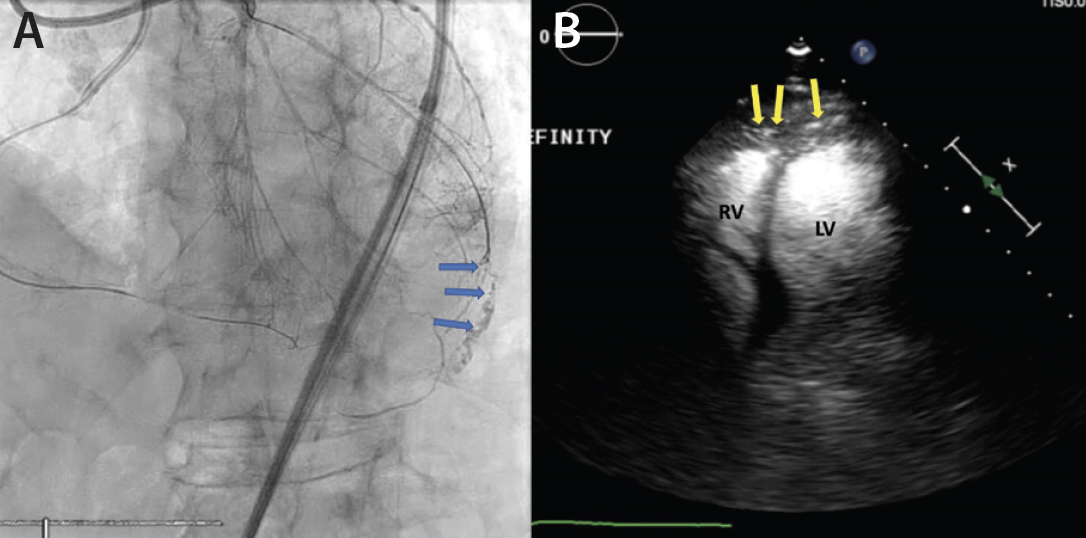

A man in his late 80s with a history of ischemic cardiomyopathy and angina refractory to optimal medical therapy presented for right coronary artery CTO PCI. The procedure required a retrograde approach via an epicardial collateral, which resulted in a coronary wire perforation of the diagonal branch (Figure 2A, Video 3). Autologous fat embolization was performed via a microcatheter, and the patient remained stable, but it was unclear whether an adequate seal was achieved. CEE was performed with an intracoronary injection of a UEA, revealing UEA filling the pericardium (Figure 2B, Video 4). Ultimately, a pericardial drain was placed and the perforation was sealed with coils.

Figure 2. Angiography after retrograde wiring via the epicardial collateral revealing a diagonal branch coronary artery perforation (blue arrows) (A). Transthoracic echocardiography after intracoronary injection of the ultrasound enhancing agent; the radiopaque microbubbles can be seen filling the pericardial space (yellow arrows) suggestive of continued bleeding into the pericardium (B).